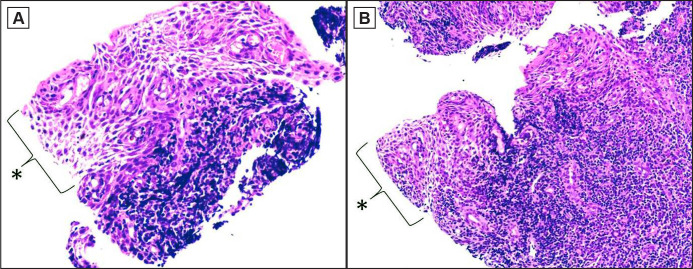

Results: Microscopic examination and cytokeratin 19 immunopositivity confirmed the diagnosis of spongiotic gingival hyperplasia. The parents of the patient declined any further intervention, and four months later the gingival lesions, including the biopsied area, did not show any significant difference from the initial examination.